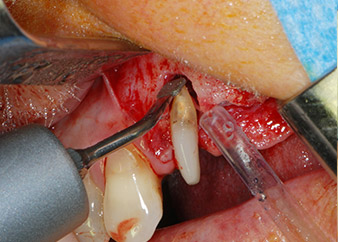

Einen Monat nach dem Eingriff waren sowohl die Schmerzen als auch die Entzündung an Zahn 24 minimal, die Zahnbeweglichkeit lag jedoch noch bei Miller-Klasse 2. Nach Freilegung und Reinigen des infizierten periapikalen und periradikulären Gewebes wurde das Ausmaß des Knochendefizits deutlich (Abb. 2 und 3).

An der bukkalen Wurzel fehlte der gesamte vestibuläre und distale Knochen. Das Attachment beschränkte sich weitgehend auf die palatinale Wurzel, was die anfängliche schlechte Prognose unterstreicht. Auch Zahn 27 wies ein verringertes horizontales Attachment (vgl. Abb. 12) und eine kleine apikale Aufhellung (Abb. 1) auf, allerdings ohne klinische Symptome.

kompletter Verlust von Knochen und Attachment

Abb. 2 und 3: Bei der Freilegung einen Monat nach endodontischer Revision und Beginn einer systematischen Parodontalbehandlung weist die bukkale Wurzel des Zahns 24 einen kompletten Verlust von Knochen und Attachment auf.

Zunächst wurde in einem Versuch, das Paro-Endo-Problem zu lösen, an der verbleibenden Wurzeloberfläche ein vorsichtiges Debridement mit einem piezochirurgischen Gerät vorgenommen (Piezomed, W&H) (Abb. 4); dann wurde der Apex mit dem gleichen Instrument im Sinne einer WSR abgetragen, um das verbleibende infizierte apikale Gewebe zu entfernen (Abb. 5). Eine retrograde Füllung war nicht notwendig, da die orthograde Füllung gerade revidiert worden war.

bukkale Wurzelspitze

Abb. 5 ... und die bukkale Wurzelspitze mit dem gleichen Instrument abgetragen (WSR).